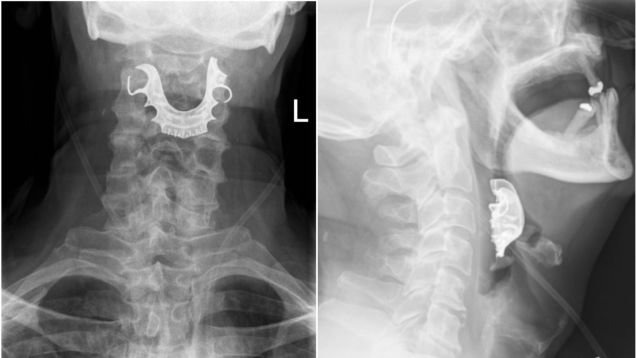

Here’s a story that’ll haunt you into your golden years. Doctors say their elderly patient endured a nightmarish week of his throat bleeding out and weeks more of surgeries and hospital care, all because surgeons had forgotten to remove his dentures—dentures that then became lodged in his throat.

Source: Gizmodo – A Man’s Dentures Got Stuck in His Throat During Surgery, Leaving Him Bleeding for Weeks